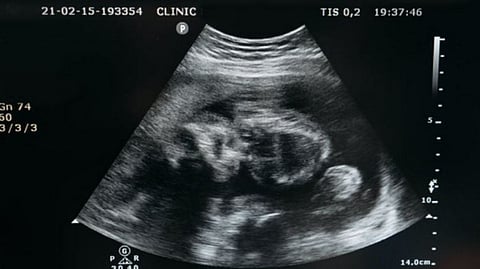

The first comes with its own set of points: initially, the growth of human shoulders slows down just before birth and speeds up thereafter; next, this phenomenon alleviates the problem of shoulder dystocia, where the shoulders interfere with the safe passage of the fetus through the birth canal.

"It is important to note that the second point reconciles the incompatibility of wide shoulders with the narrow birth canal. The shoulders show an 'intelligent' modification in fetal development," notes lead author PhD candidate Mikaze Kawada.

The team then looked at different shoulder-width to birth-risk correlations between humans and the two other primates. Chimpanzees have proportionally large shoulders and yet, like macaques, fewer shoulder-related birth complications. Since chimpanzees move about less frequently on two feet, their pelvis -- and therefore their birth canal -- is larger than that of their human counterparts.